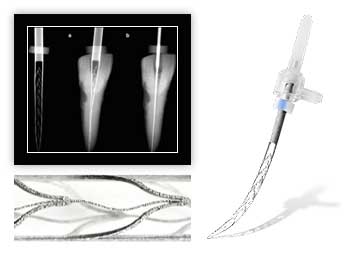

- Каналы пломбируются. При необходимости восстанавливается коронка зуба или в каналы устанавливается штифт, в дальнейшем будущий основой для зубного импланта.

Отдельно стоит отметить анатомическую особенность некоторых зубов с невероятно длинными и ветвистыми каналами, которые невозможно обработать качественно. В этом случае лечение тоже не может быть осуществлено.